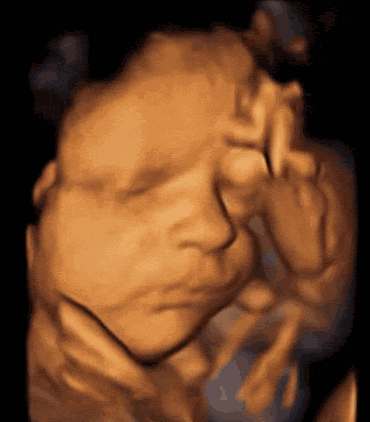

让准妈妈及家属直观地看到胎宝宝

打哈欠、吸吮、揉眼睛等可爱动作固然重要,

但更重要的还是四维彩超的“排畸”功能

有些妈咪发现,同样是做四维

为什么别人家的宝宝表情多变还清晰?